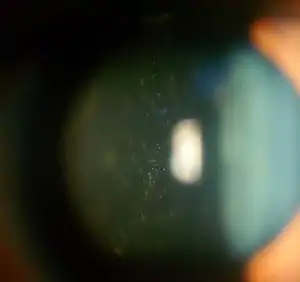

| Anterior vitreous cells in Intermediate uveitis | |

Intermediate uveitis is a form of uveitis localized to the vitreous and peripheral retina. Primary sites of inflammation include the vitreous of which other such entities as pars planitis, posterior cyclitis, and hyalitis are encompassed. Intermediate uveitis may either be an isolated eye disease or associated with the development of a systemic disease such as multiple sclerosis or sarcoidosis. As such, intermediate uveitis may be the first expression of a systemic condition. Infectious causes of intermediate uveitis include Epstein–Barr virus infection, Lyme disease, HTLV-1 virus infection, cat scratch disease, and hepatitis C.

Pars planitis is considered a subset of intermediate uveitis and is characterized by the presence of white exudates (snowbanks) over the pars plana or by aggregates of inflammatory cells in the vitreous (snowballs) in the absence of an infectious or a systemic disease. Some physicians believe that patients with pars planitis have worse vitritis, more severe macular edema, and a guarded prognosis compared to other patients with intermediate uveitis.